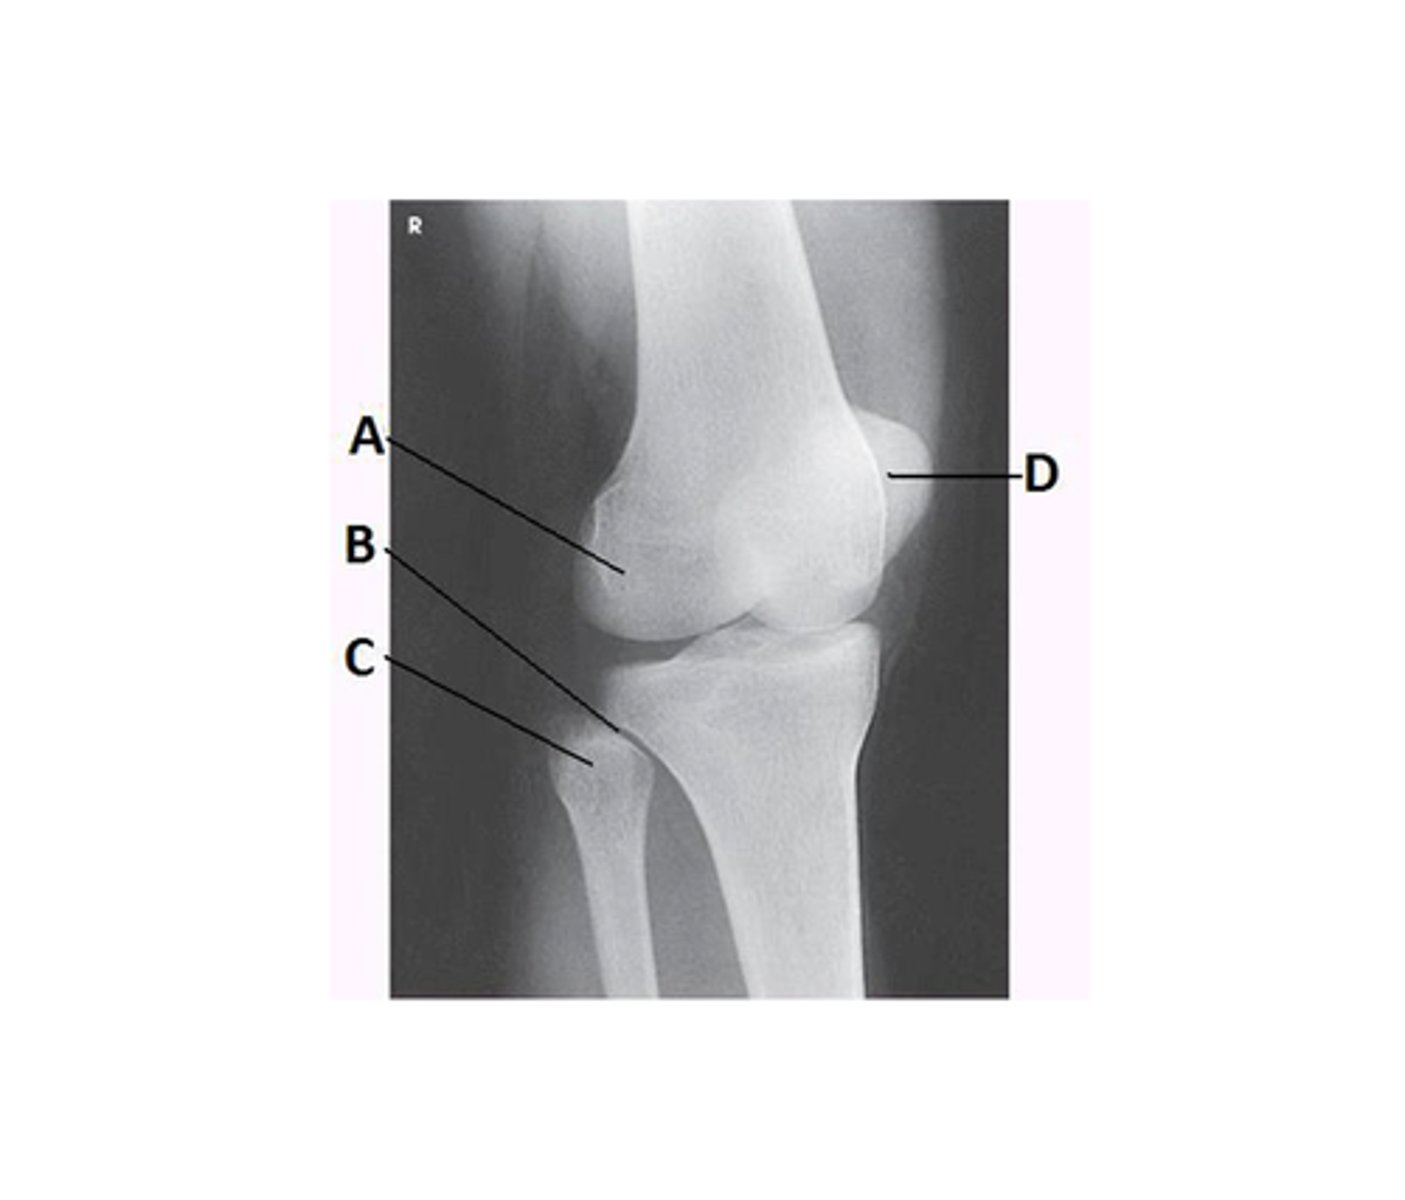

What projection is demonstrated in the image below?

AP oblique knee with medial rotation

Tibiofibular articulation

Which of the following is clearly demonstrated on an AP oblique projection of the knee in medial rotation?

Proximal tibiofibular joint

What anatomy is labeled with the letter B in the image below?

Lateral femoral condyle

What anatomy is labeled A in the image below?